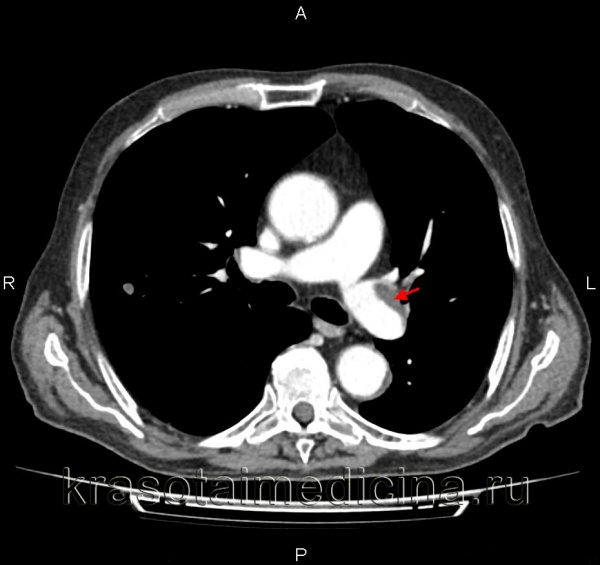

КТ-ангиография легочных артерий. Протяженный пристеночный тромб в просвете основного ствола левой легочной артерии